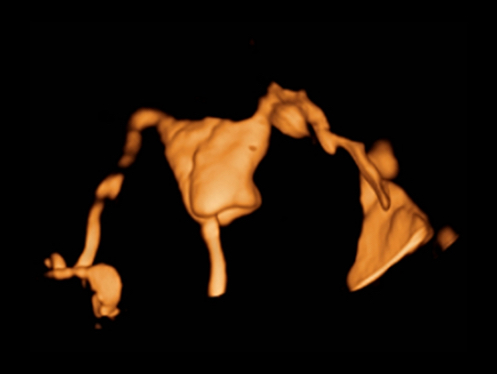

Obrazy kliniczne